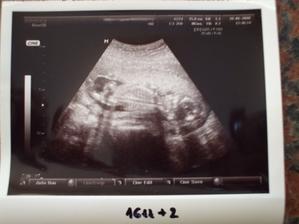

Náš červíček

Ondrík je medzi nami...